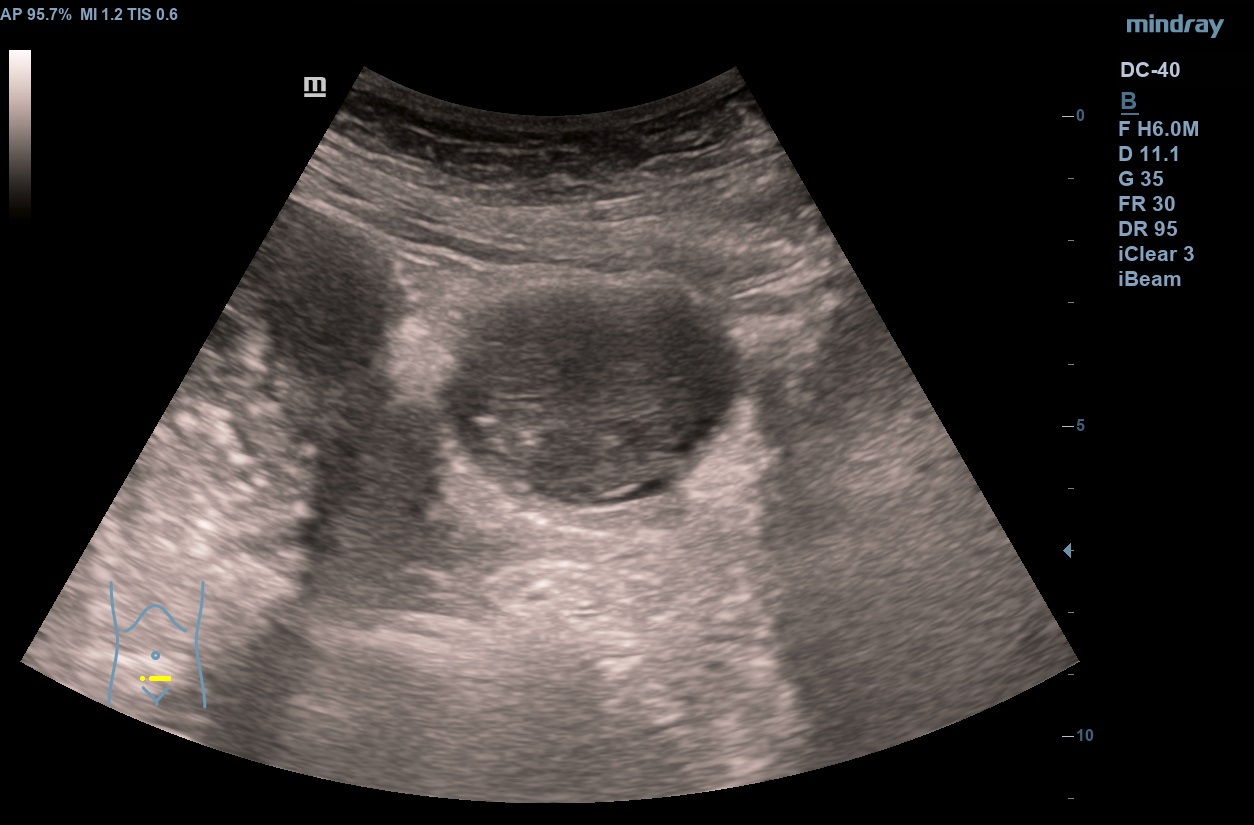

Hallazgos ecográficos

En analítica de control por Cardiología se evidencia anemia microcítica hipocrómica. En el estudio de la misma y concomitando con una infección de orina, se objetiva microhematuria, si bien no reseñable. Se trata la infección de orina y dada la desaparición de la sintomatología y la buena respuesta a tratamiento con ferroterapia, se cesa el estudio. Repite en dos ocasiones más ITU + microhematuria. Dada la continuidad de los episodios, realizamos ecografía en AP objetivando la presencia de una LOE intravesical, que se estudia en el ámbito hospitalario confirmado el diagnóstico de ca. uroterial.

Ecografía en AP: sospecha de tumoración intravesical. TAC abdómino pélvico: masa vesical dependiente de pared izquierda con hipercaptación, impresiona de diseminación a distancia. Uro-TC confirma ca. de vejiga. AP con carcinoma uroterial papilar de alto grado G3pT1. Estudio de extensión por el momento negativo.